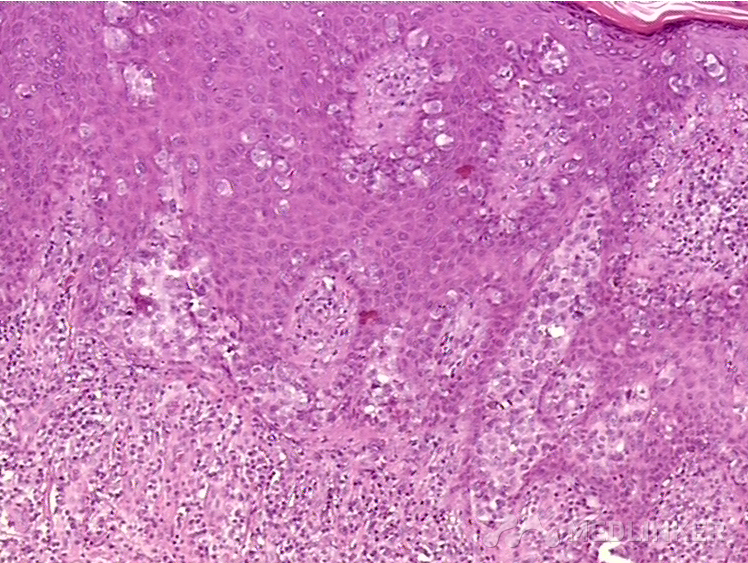

乳房外佩吉特病

后来我建议他做了活检,病理结果显示【乳房外Paget病】!

乳房外Paget病是一种什么样的疾病呢?原来它还有一个名字,就叫湿疹样癌,长的就是很像湿疹,但是按照湿疹怎么样也治不好!所以各位医生,如果觉得有自己治疗不好的顽固性湿疹,可能不是咱水平不行,是因为这个病不是湿疹,所以照着湿疹治疗效果肯定不好了。 另外如果得了阴囊湿疹持续超过半年一直不好的话,建议去医院皮肤科做病理活检。因为炎症和肿瘤的区别就是炎症是可以消退的,可以好一段时间再犯,而肿瘤是始终存在的,通过外用药膏是无法治疗好的。大家记住这个重要的鉴别点好了,【肿瘤是会持续存在的,药膏是治疗不好的】。 这个病的治疗并不困难,需要排除远处转移的肿瘤,发现了扩大切除,预后都会不错的。